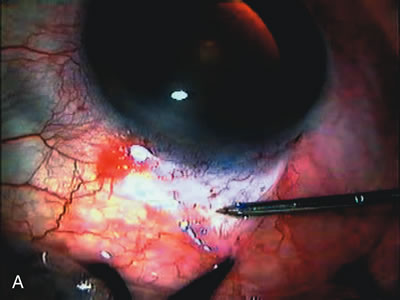

In years past, patients with both cataract and glaucoma frequently provided overwhelming surgical challenges for the ophthalmologist. The ability to carry out phacoemulsification through a 3.2-mm corneal incision along with inserting a foldable IOL is a vast improvement over 11-mm incisions that were common a decade ago (Fig. 1). The anatomical and inflammatory changes to the eye are less with small incision techniques, improving the likelihood of success with concomitant glaucoma surgery. Pharmacologic inhibition of fibrosis along with postoperative wound revision increases the long-term success rate of filtration surgery when combined with lens extraction. (Fig. 2). The learning curve may be steep at times, but the blending of cataract and glaucoma surgical skills slowly falls into place as the surgeon constantly learns and upgrades his or her technique.

Fig. 1. The anatomic advantage of small incision cataract surgery for the glaucoma patient. A. Long-term bleb function with a large cataract incision is difficult to achieve with either ECCE-trabeculectomy or trabeculectomy followed later by ECCE. This bleb failed to form sufficiently when combined with large incision ECCE. The inflammation, bleeding, and long-term wound healing with stimulation of fibroblasts associated with this technique are more likely to cause bleb failure. In addition, the increased iris manipulation necessary to deliver the nucleus and subsequent iris repair adds to the long-term breakdown of the blood aqueous barrier. B and C. Two-site phacotrabeculectomy has the advantage of small incision cataract surgery combined with separate site trabeculectomy. The incision size is one third the size of the standard ECCE. The inflammation is less severe, and cataract wound healing is confined to the temporal area. Visual rehabilitation with phacoemulsification and foldable IOL is much faster. Phacoemulsification allows successful lens extraction even in the unfriendly environment of a smaller pupil compared with ECCE. The trabeculectomy is performed in an entirely different site, well away from the wound healing associated with temporal phacoemulsification. The likelihood of this filter functioning long-term is greater than with ECCE-trabeculectomy. D. The surgeon also has the option of single-site phacotrabeculectomy with foldable IOL. Both the lens extraction and trabeculectomy are performed through one small 3.5-mm limbal incision.